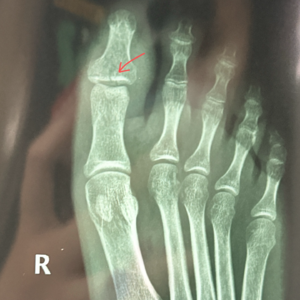

检查拍x光日。

00:13 终于去医院拍片检查了

02:08 太懂了😭😭当时双拐去复查,东拐西拐地来到二楼的科室、然后又要去隔壁楼、隔隔壁楼拍片……